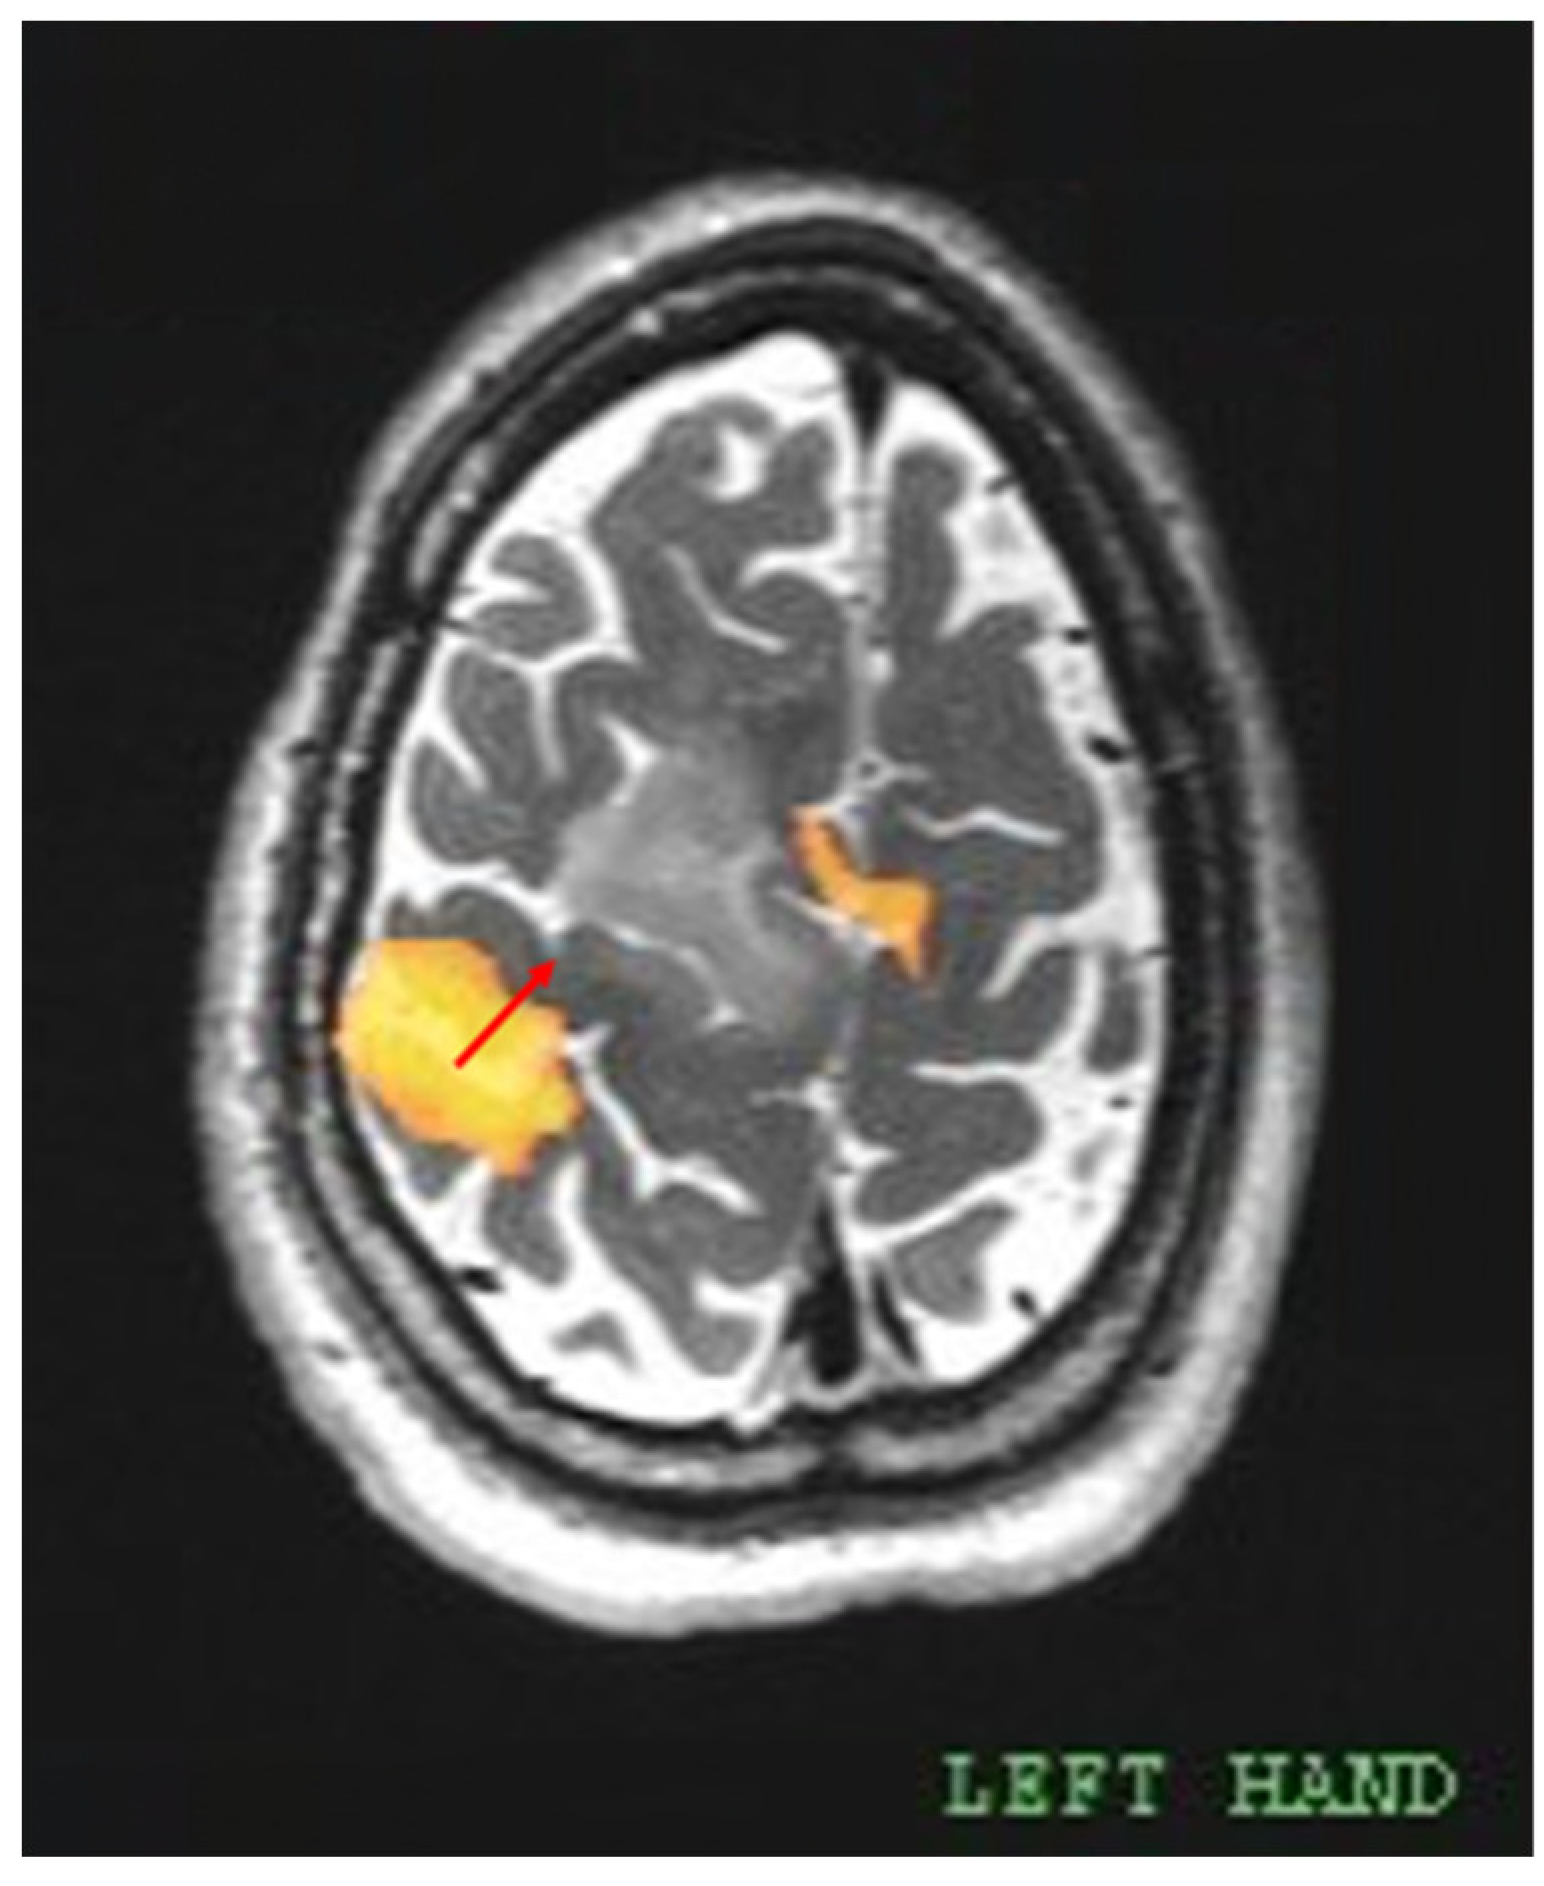

The fMRI images were uploaded to the neuronavigation station, allowing intraoperative recognition of the eloquent areas. For this study, the minimum distance between the area of primary motor cortex (PMC) functional activation and the tumor was measured as shown in Figure 2. Each activation located on the central sulcus was considered to represent the PMC. Common anatomical landmarks such as the omega sign (“hand knob”) were used to identify the central sulcus on axial images. Among different motor tasks, only those that evoked a cluster of activation nearest to the tumor were considered significant. Similarly, if more than one cluster of activation was evoked by the same motor task, only the one closest to the tumor was considered.

Figure 2. The distance was measured between the center of mass (COM) of the activation cluster, which was evoked by a left-hand motor task at the PMC, and the edge of tumoral signal abnormality. The resulting distance was found to be 18.72 mm (red arrow). Another cluster of activation, located anteromedial to the tumor, was identified as the SMA. Carestream Vue PACS software (ver. 11.4.1.0324, Carestream Health, Rochester, NY, USA).